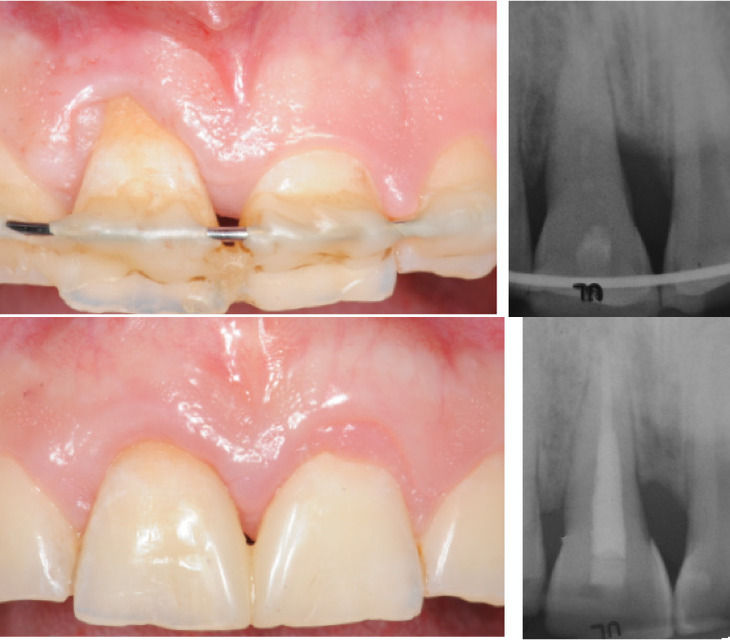

Une nouvelle procédure, combinant une technique de préservation papillaire avec greffe de tissu conjonctif et lambeau déplacé coronairement, sera présentée. La greffe de tissu conjonctif joue le rôle de paroi vestibulaire du défaut intra-osseux, traité par apport d’amélogénines, augmentant ainsi la stabilité du caillot

sanguin pour favoriser la régénération parodontale et améliorer le résultat esthétique.

3) Est-il réellement possible d'améliorer les résultats esthétiques lors d’une chirurgie de régénération?